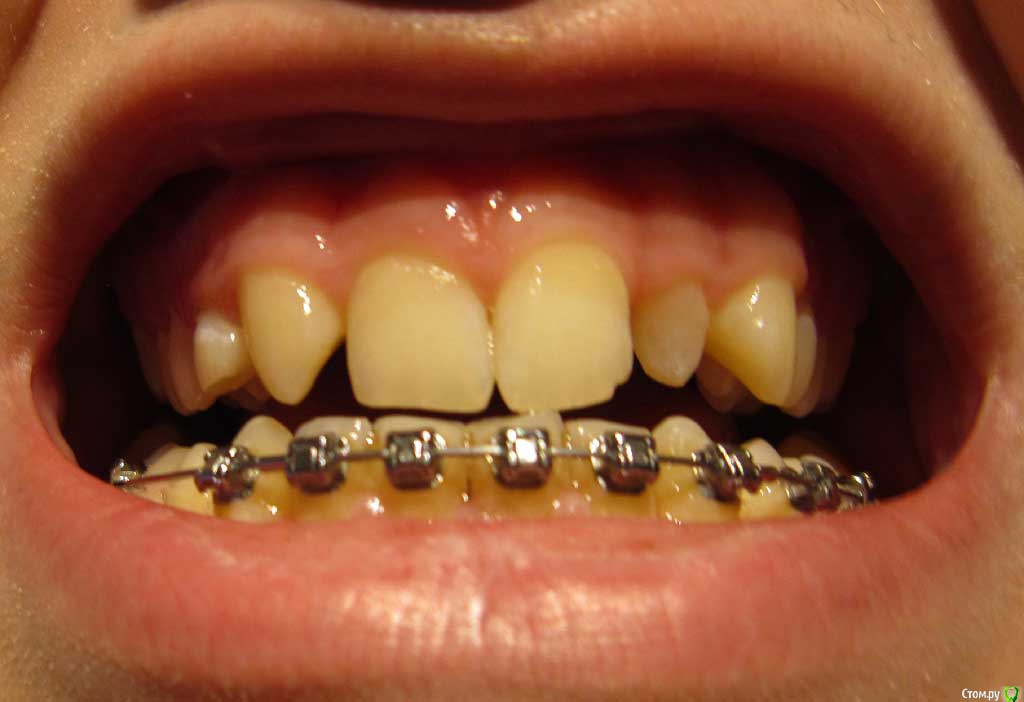

Сейчас мне 17 лет. На лечении у ортодонта с августа 2013 года. Удалили молочные пятерки и стали сдвигать шестерки к передним зубам. На верхнюю челюсть она ставить брекеты не стала. Осенью 14 года врач ушла в декрет.

Пришел новый врач который предложил все сделать несколько иначе: поставить брекеты на обе челюсти, все выравнять и освободить место под будущие импланты: вместо пятерок снизу и второго слева резца сверху -, а пока на их место поставить коронки. Также врач назвал сроки: около 1 года.

Сверху слева отсутствует зачаток второго резца, вместо него находится клык и молочный зуб левее. Внизу нет зачатков пятерок.